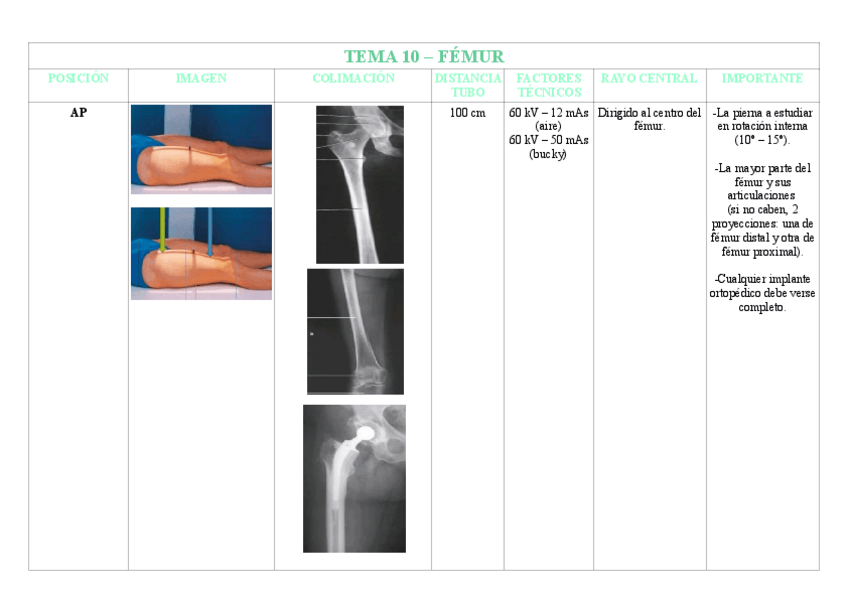

TEMA-10-FEMUR.pdf

3 páginas